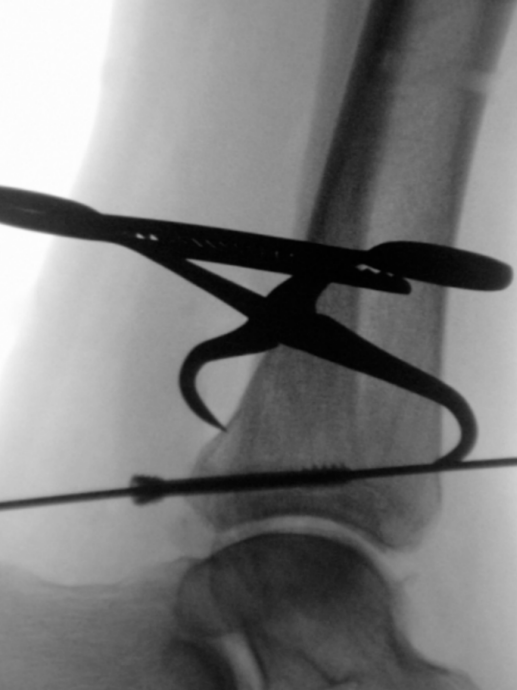

仔细行骨膜下剥离后,显露后踝骨折,清除嵌入的软组织,使用尖头复位钳进行解剖复位并临时固定(图3a)。确认复位满意后,于胫骨平台外侧三分之一、骨骺瘢痕近端确定导针进针点。此位置允许建立垂直于骨折平面的由后向前螺钉轨迹,从而在**化加压的同时避免关节内穿入。

经一长约1厘米的纵向皮肤切口,显露胫骨前侧皮质。在透视引导下,并使用两把小号Longbeck拉钩保护伸肌腱及神经血管结构,将一枚用于4.5毫米无头双螺纹加压螺钉的1.6毫米导针,从前内侧向后外侧、以约5-10°的向远端倾斜角置入(图3b–d)。经术中三维透视确认导针位置正确后(图3e),测量所需螺钉长度。

image.png

(a)

(b)

(c)

(d)

(e)

图3. (a–e): (a) 使用尖头复位钳临时固定;(b) 从前向后置入1.6毫米导针;(c) 踝穴位片,红线标记腓骨切迹后缘,蓝线标记前缘;(d) 点状末端视图证实轨迹位于切迹外;(e) 术中三维透视显示导针正确走行。